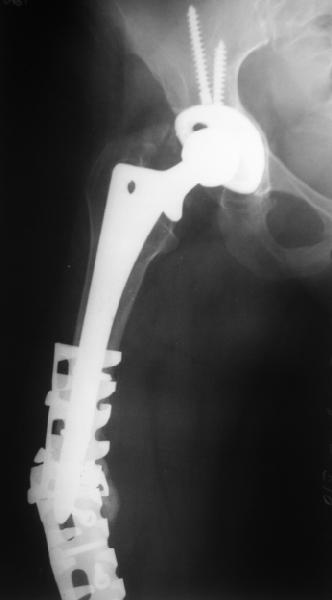

Although, there is just one view, it seems that cement is still holding well on lateral side, cup also seems to be stable, but inside is asymmetric – poly is damaged ... options:

1. "Easy": long lateral plate and anterior strut allograft w/wo bone grafting

2. "Harder" Removal of prosthesis (has to be done if it is loose in remnant of intact proof proximal femur), and new long stem, porous coated prosthesis with new cup (pt is 59years old, probable in good health – survived 6 weeks of traction… this would be my 1st option)

Female, rheumatoid, THA in 2003, car accident in 2006, failed plating. Nailing in Oct 2007. The nail is solid with hollow proximal part where the stem is docked. Last images are in 1 year after

nailing.